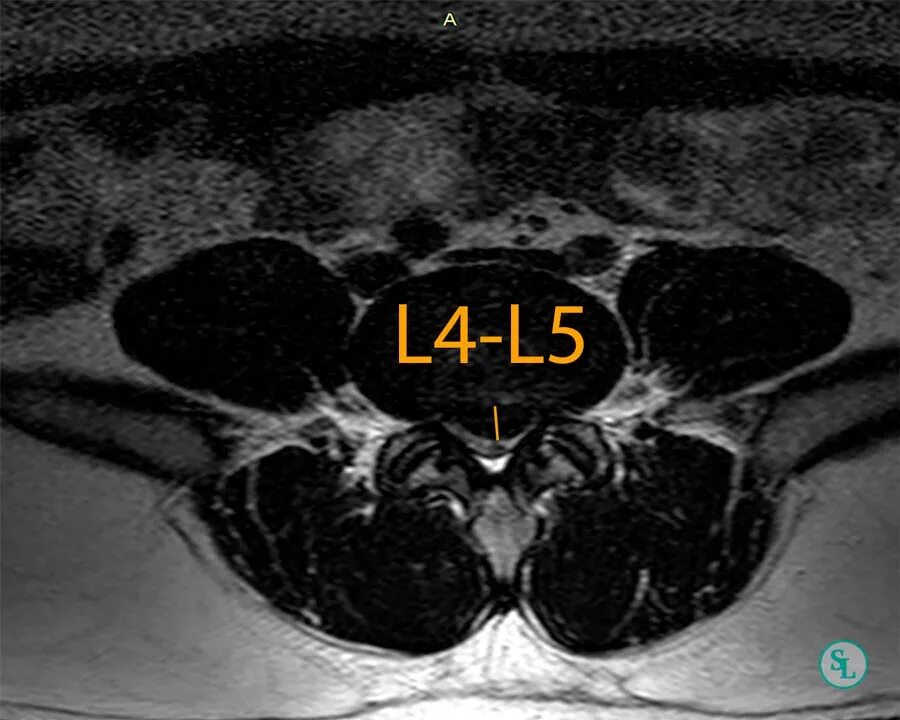

Операция удаление грыжи l5 s1